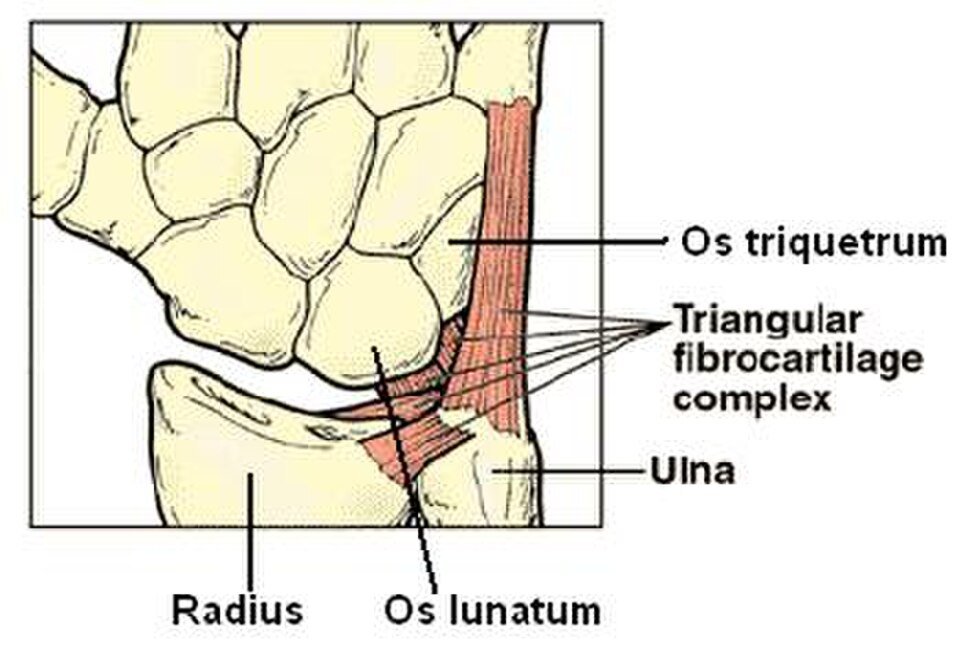

Lesão da Fibrocartilagem Triangular (TFCC): O Que Causa Essa Dor no Lado do Punho

Lesão da fibrocartilagem triangular é uma das causas mais comuns de dor no punho do lado do dedo mínimo. Se você sente dor ao girar